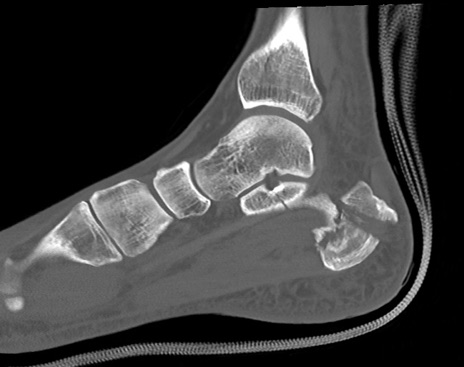

症例37 左足関節CT(矢状断像)

左足関節CT